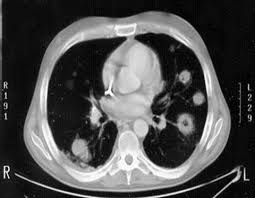

►Chụp chụp cắt lớp vi tính vùng ngực (CT SCAN): giúp phát hiện hình dạng, kích thước, vị trí chính xác của khối u, đánh giá mức độ xâm lấn các cơ quan lân cận như: hạch trung thất, màng phổi, xương sườn, gan…qua đó giúp đánh giá giai đoạn của bệnh.